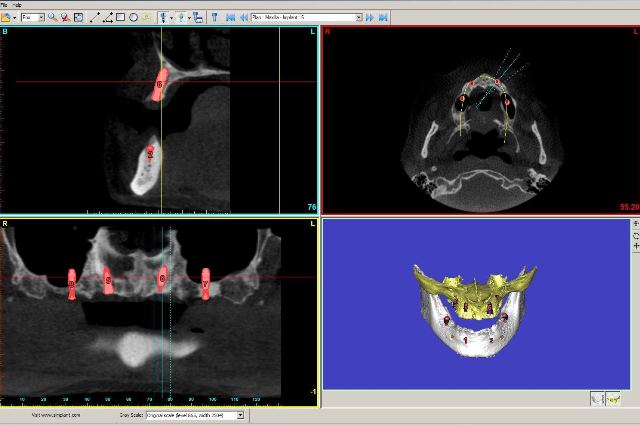

Za razliko od običajnih CT-naprav, kjer rentgenski snop prodira skozi tkivo v ravninah in slika nastane z obdelavo vseh »rezin«, ki so različno narazen (običajno 1 do 3 mm), pri CT-napravah s stožčastim snopom detektorji sprejemajo stožčast snop – podatki dajo sliko prostornine in ne samo ravnine. Naprave so precej manjše, pacientu ni treba ležati, odmerek sevanja, ki ga prejme pacient, je okrog 50-krat manjši, kot pri običajnih CT preiskavah, slika trdih tkiv (torej kosti in zob) pa je neprimerno ostrejša (slike 2, 3, 4).

Slike 2, 3, 4: Posnetki CT-ja s stožčastim snopom. Položaj nadštevilčnega zoba je jasno prikazan v vseh treh ravninah, lepo se vidi, da zob s krono sega v nosno votlino. Zob je mogoče natančno izmeriti.

Ko imamo posnetke v digitalni obliki, jih lahko s primerno programsko opremo obdelujemo na najrazličnejše načine. Kirurg lahko na svojem računalniku natančno izmeri razdalje, ki ga zanimajo, in tako pripravi natančen načrt zdravljenja. S posebno programsko opremo je mogoče že na računalniku simulirati operacijo in opazovati predvideni klinični rezultat. V implantologiji je tako mogoče prikazati čeljustnice v 3D-obliki in simulirati vstavljanje določenih implantatov. Program nam jasno pokaže kritične anatomske strukture (živec v spodnji čeljusti, obnosni votlini v zgornji čeljusti…). Tako je že pred posegom jasno, pod kakšnim kotom je potrebno vstaviti implantate, katera mesta v kosti so najprimernejša za vstavitev in katera debelina in dolžina implantatov sta najprimernejši (slika 5).